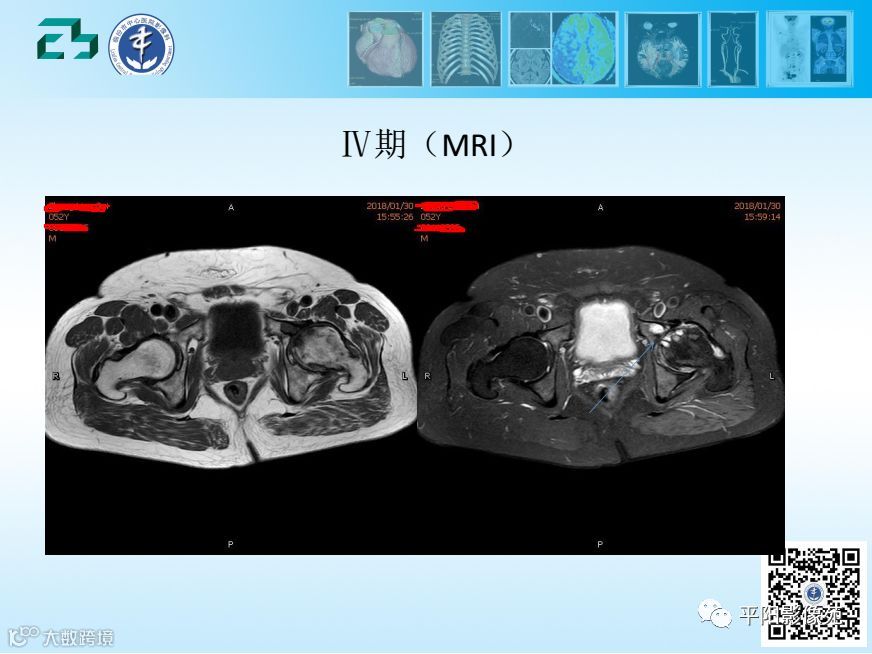

【影像基础】股骨头缺血坏死分期